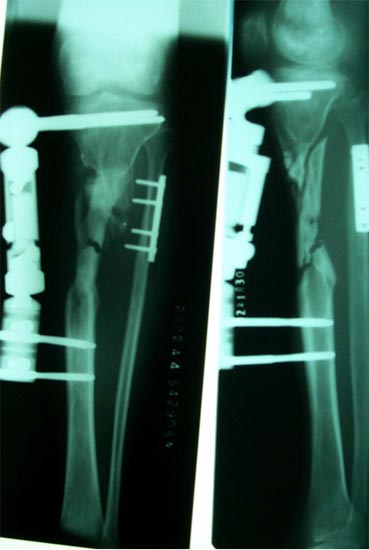

病例二 患者男性,45岁,胫骨上段开放粉碎骨折2年,骨不连

图2-1病例二、患者男性,45岁,胫骨上段开放粉碎骨折2年,骨不连。我们用带锁髓内钉固定骨折端提供支撑力,患者自体骨髓细胞经与松质骨和骨生长因子复合,使没有细胞的植骨材料变成了有细胞的活骨。骨折在9个月后愈合。